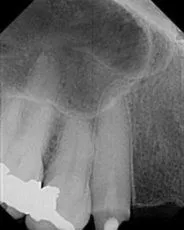

Cosmetic Composite Filling

Before

After